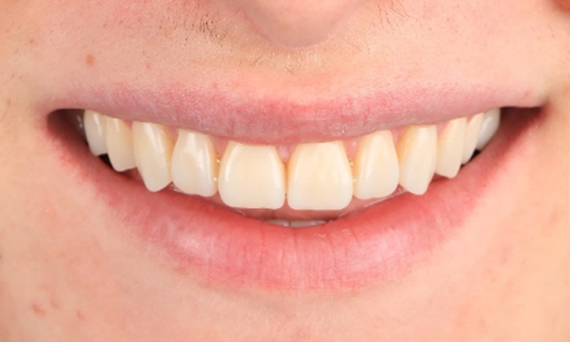

Amélogenèse imparfaite

Restauration complète de la bouche avec 28 restaurations tout céramique

Un cas particulier et prolongé de malocclusion squelettique de classe II et d’amélogenèse imparfaite généralisée chez un adolescent a été référé pour une réhabilitation prothétique. L’objectif du traitement était de préparer la structure dentaire restante, d’éliminer les contre-dépouilles et de faire de la place pour des couronnes entièrement en céramique couvrant toute la dentine et simulant l’émail perdu.

Après : Résultat final, 1 semaine après l’opération.